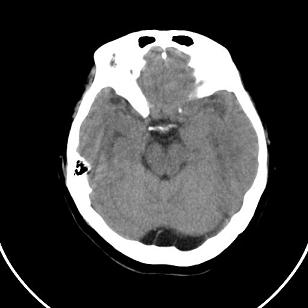

小脑后的囊状低密度影,里面可见分隔,考虑枕大池还是蛛网膜囊肿。

双侧脑室外缘灰质密度结节应该是尾状核的体部;枕大池前缘受压前移位,考虑囊肿

支持灰质移位,mri检查有必要.枕大池蛛网膜囊肿.

1)脑灰质异位。2)双侧枕部颅骨内板下方类似扇形及弧形脑脊样低密度影;鉴别于巨大枕大池与蛛网膜囊肿之间。建议必要时行进一步检查。

支持 1灰质移位,2枕大池蛛网膜囊肿。

支持灰质移位,mri检查有必要.枕大池蛛网膜囊肿